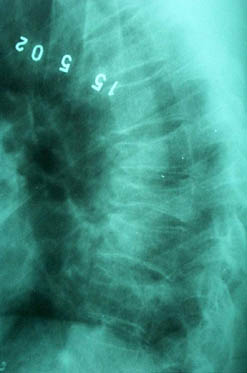

В декабре 99 года перенес геморрагический а потом и ишемический инсульт левой задне-лобно-височной области. Выписался со значителсным улучшением неврологической симптоматики. Через год, на фоне обычного самочувствия, пожаловался на боль в спине, после чего появилось тоническое напряжение правой руки, половины туловища, перерастающее в приступ с судорогами по типутонико-клонических и потерей сознания. Госпитализирован. На CТ выявлен большой очаг в виде кистозной полости. Компрессионный перелом 8-9 грудных позвонков. В последующем, на протяжении полутора лет в общей сложности отмечено 5 аналогичных по формуле припадков. Падения с высоты во время приступов небыло. Также отрицает травмы позвоночника в анамнезе. ПовторнаяR-графия и СТ позвоночника выявила патологический компрессионный перелом и остеопороз тел Th 6; 7; 8; 9, (отрицательная динамика). Наличиенеобластомного процесса не выявлено. Все анализы, включая паратгормон, впределах нормы кроме:Са-Т - 2.66 (от 2.02 до 2.60)Р - 1.72 (от 081 до 1.62)СОЭ - 34мм/часСнимки 1, 2, 3, 4 прилагаются.Возникает ряд вопросиов: Может ли деструкция в левой задне-лобно-височной области быть связана с системним остеопорозм позвонков и пат. переломом? Моигут ли эпилптические приступы явиться причиной компрессионного переломапозвонков? Какие дополнительные исследования нужны для дифдиагностики болезни Куммелля? Тактика лечения (корсет?), показания и противопоказания к хирургическому вмешательству на позвонках в данной ситуации Прогноз?Буду благодарен любым соображениям,Аршак Мирзоян